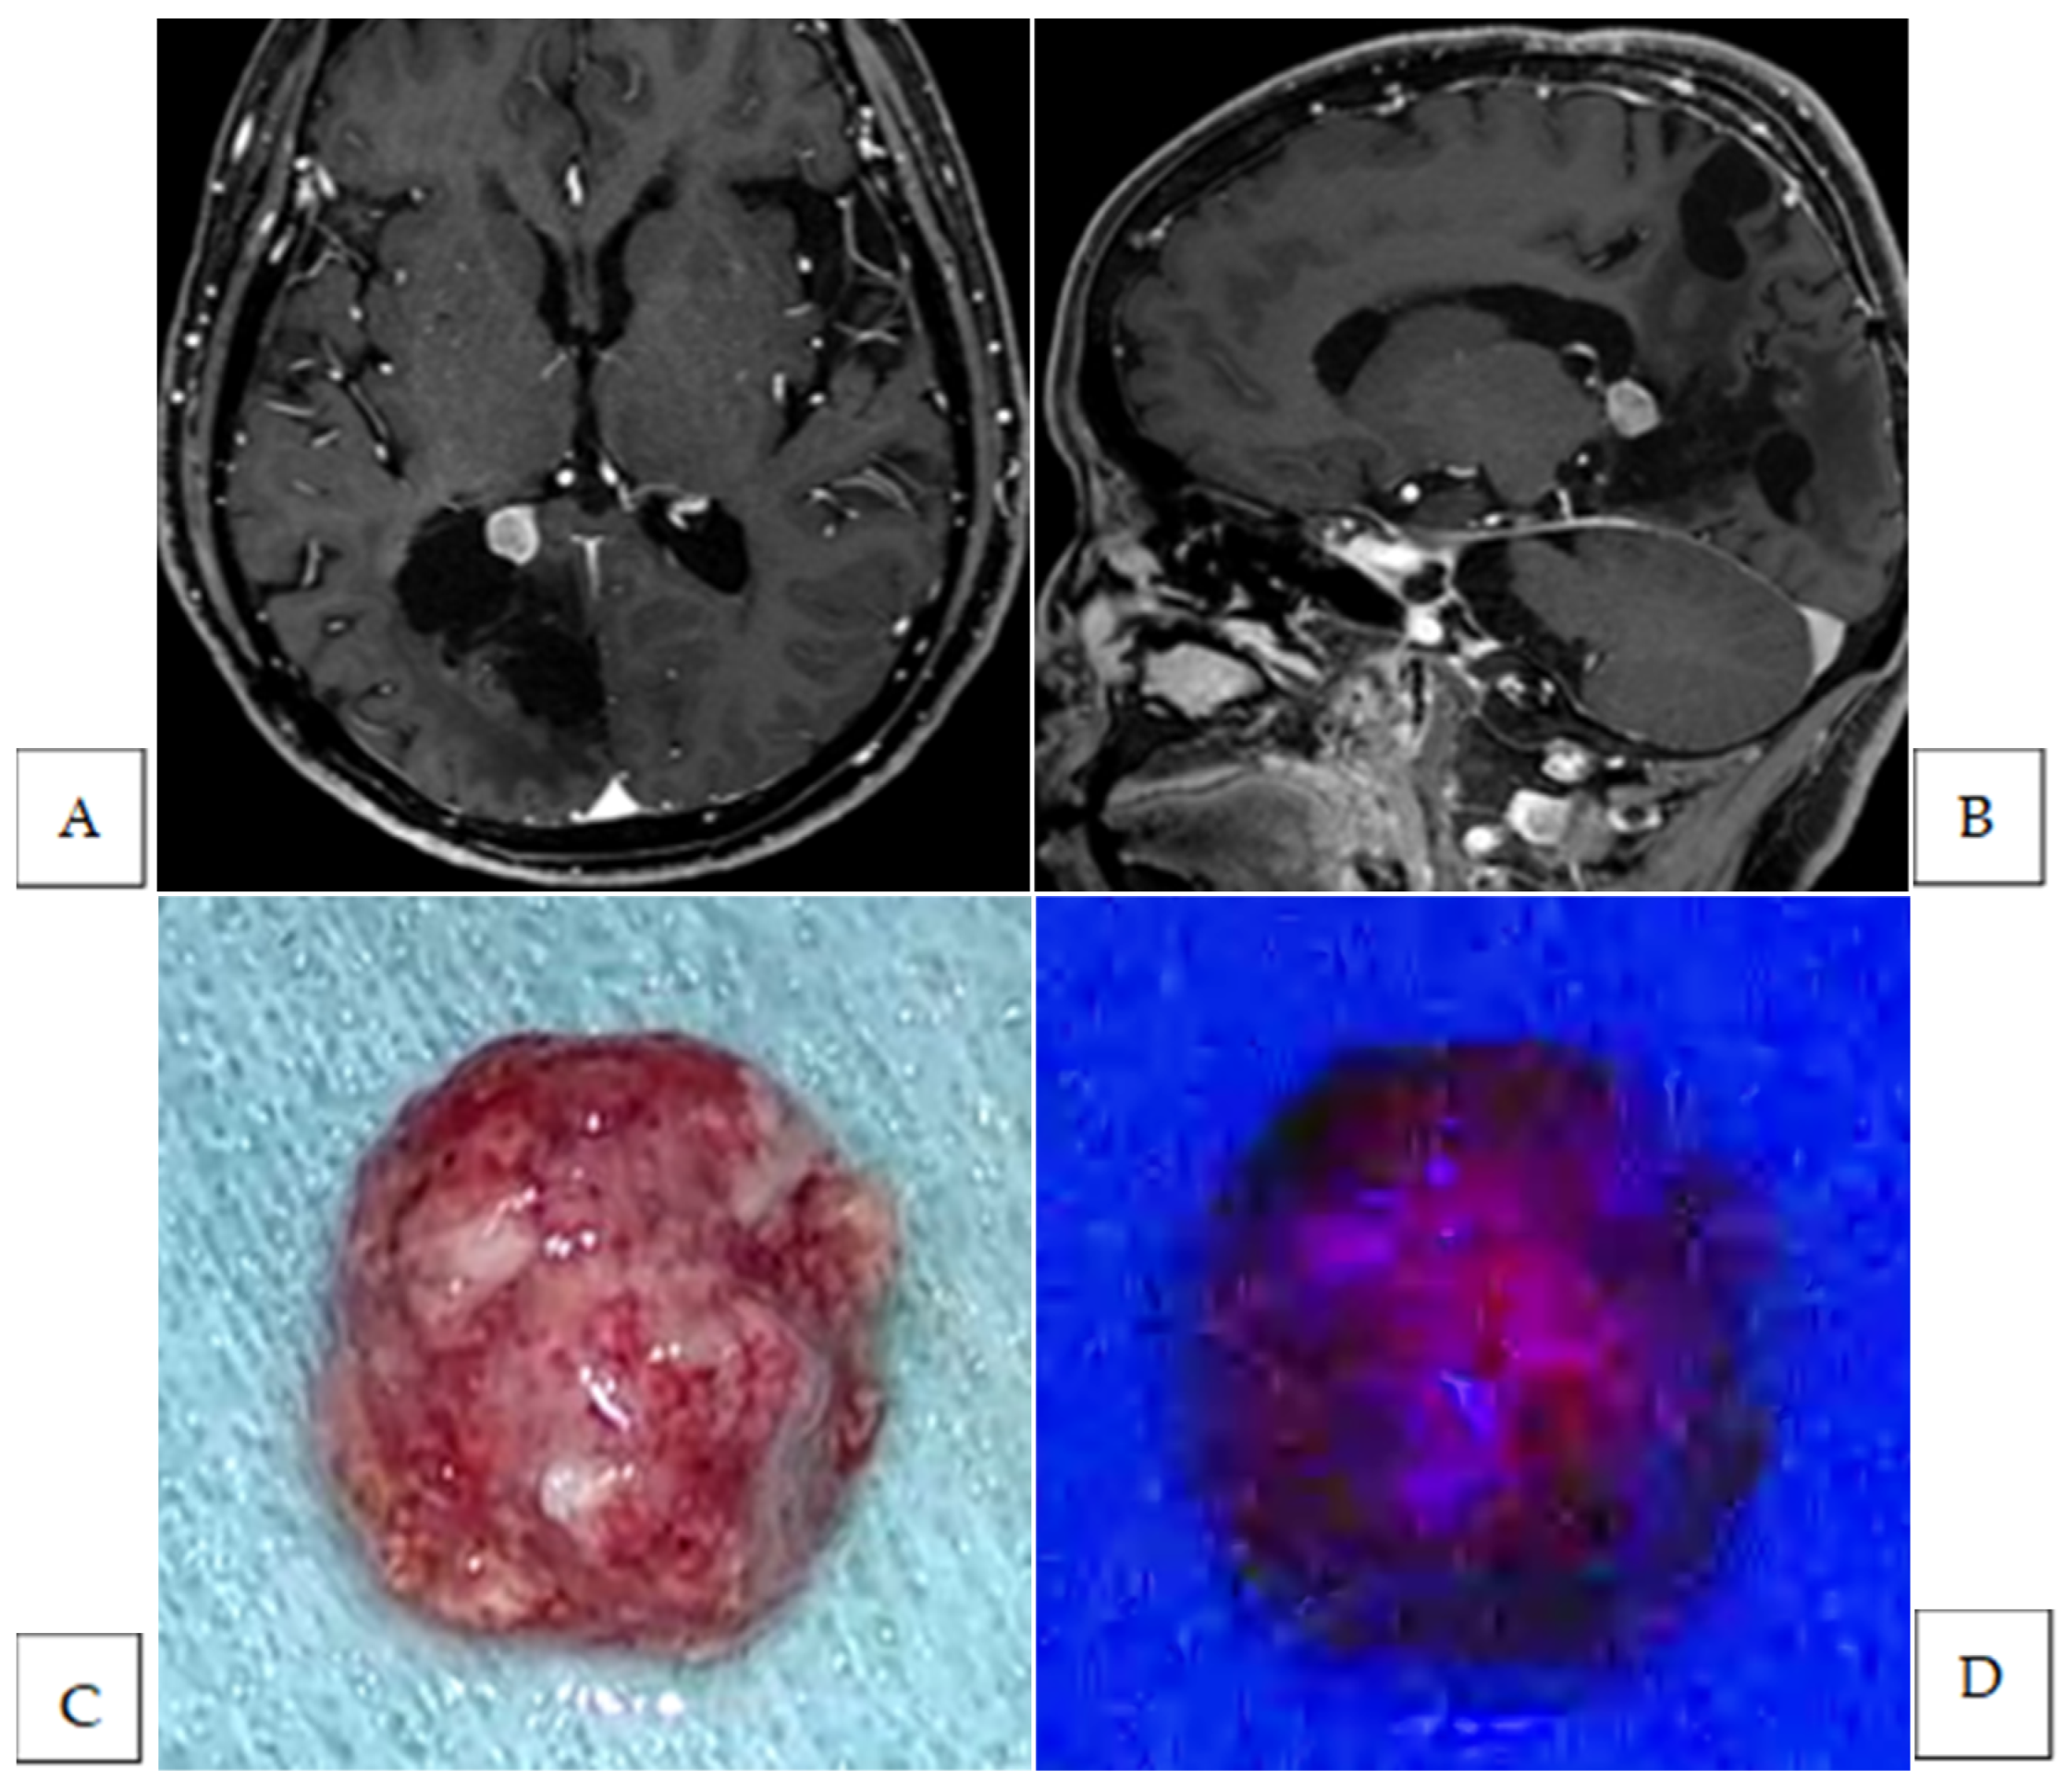

| 1 | olfactory groove | meningothelial | None | |||||

| 2 | parasagittal | atypical | Strong | yes | yes | brain | 2 | no |

| 3 | planum sphenoidale | meningothelial | Strong | yes | yes | brain | 1 | no |

| dura | 1 | yes | ||||||